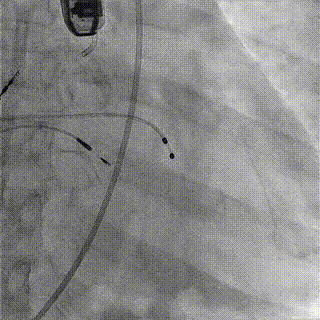

术中影像

1.主动脉根部造影,可见大量反流

2.输送系统过主动脉弓

3.输送系统造影定位

4.释放瓣膜

5.瓣膜完全释放

6.最终造影,反流消失

手术结果

术后食道超声及造影未见瓣周漏,效果良好,手术圆满完成。

瓣膜释放后,食道超声及造影均提示瓣膜无残余反流。